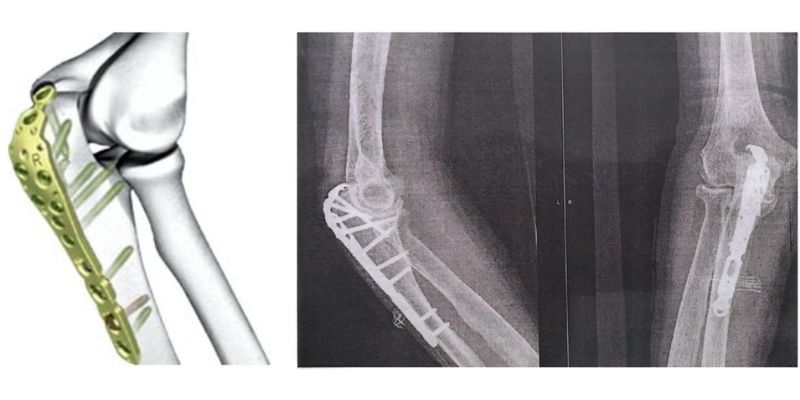

1. Κατάγματα κονδύλων και επικονδύλων βραχιονίου

Τα κατάγματα αυτά είναι ιδιαίτερα συχνά σε παιδιά και συχνά επηρεάζουν την αρθρική επιφάνεια.

Αντιμετώπιση:

- Χειρουργική αποκατάσταση με ανατομική ανάταξη

- Σταθεροποίηση με πλάκες και βίδες

- Σε παιδιά: προσοχή στην ανάπτυξη λόγω της παρουσίας του αυξητικού χόνδρου

Οφέλη επέμβασης:

- Άμεση κινητοποίηση

- Επαναφορά της κινητικότητας του αγκώνα

- Πρόληψη δυσκαμψίας και παραμορφώσεων